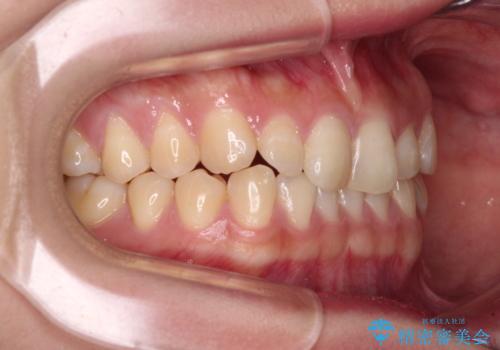

治療途中の奥歯と矯正治療の後戻り インビザライン・ライトによる矯正治療

- 根管治療を行ったままの奥歯と、矯正治療の後戻りを気にして来院された患者様です。

根管治療された歯に症状はなく、オールセラミッククラウンにて補綴治療を行うこととしました。

矯正治療の後戻りは軽微であったため、インビザラインの簡易パッケージであるインビザライン・ライトを用いて歯列を整えることとしました。

クラウンはよりよい咬み合わせで装着したいため、インビザラインを1セット使用して概ね歯列を整えた時点で補綴治療を行い、その後仕上げの矯正治療を行いました。